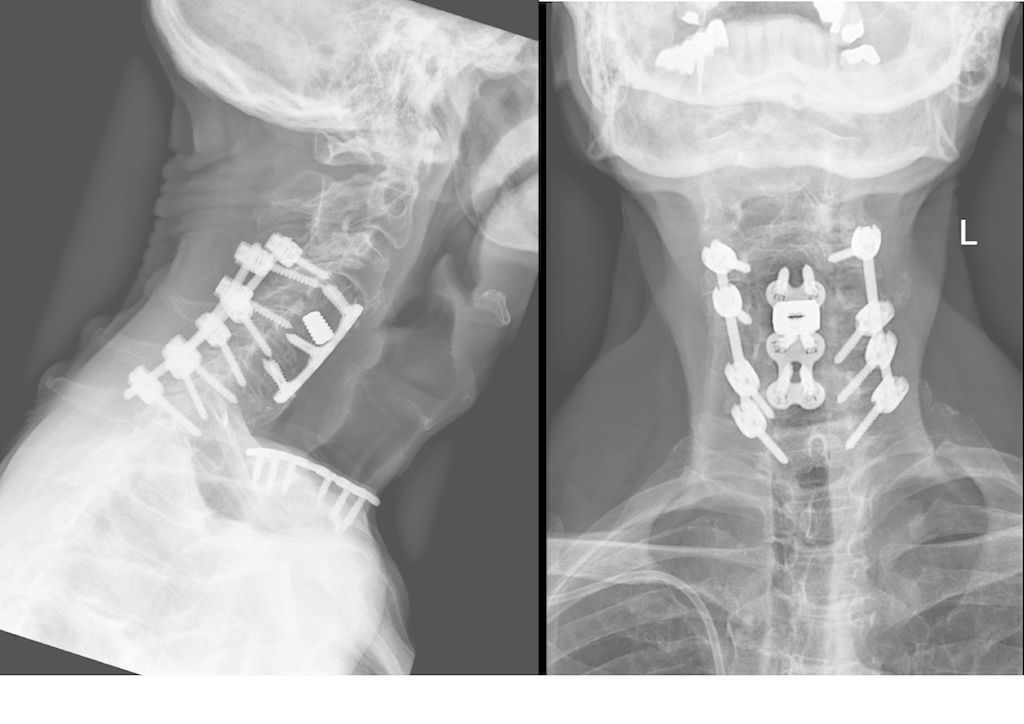

Beispiel für die Implantation zervikaler Pedikelschrauben. In diesem Fall kam es bei einem 61-jährigen Patienten 10 Jahre nach anteriorer zervikaler Diskektomie und Fusion (ACDF) C4/5 und ventraler Verplattung C4–6 zu einer Ankylosierung auch von C6/7. Nach Sturz kam es zu einer Fraktur bei C6/7 mit begleitender Bogenfraktur und auch Beteiligung der dorsalen Ligamenta (Abb. 1 und 2). Klinisch bestanden ausgeprägte Nackenschmerzen und kein neurologisches Defizit. Es wurde die Indikation der dorsalen Verschraubung von C4 auf Th1 gestellt. Intraoperativ wurde routinemäßig zusätzlich eine kleine Referenzschraube in einer Lamina – entfernt von der Dornfortsatz-Referenzklemme für die Navigation – gesetzt. Mit dieser konnte intraoperativ die Genauigkeit der Navigation exakt überprüft werden (Abb. 4 und 5). Mittels navigierter High-Speed-Fräse wurden die Schraubenkanäle vorgebohrt (Abb. 6), im Anschluss wurde der Bohrkanal ausgetastet und die Schrauben wurden implantiert. Abbildung 7 zeigt eine Röntgenkontrolle 3 Monate postoperativ.